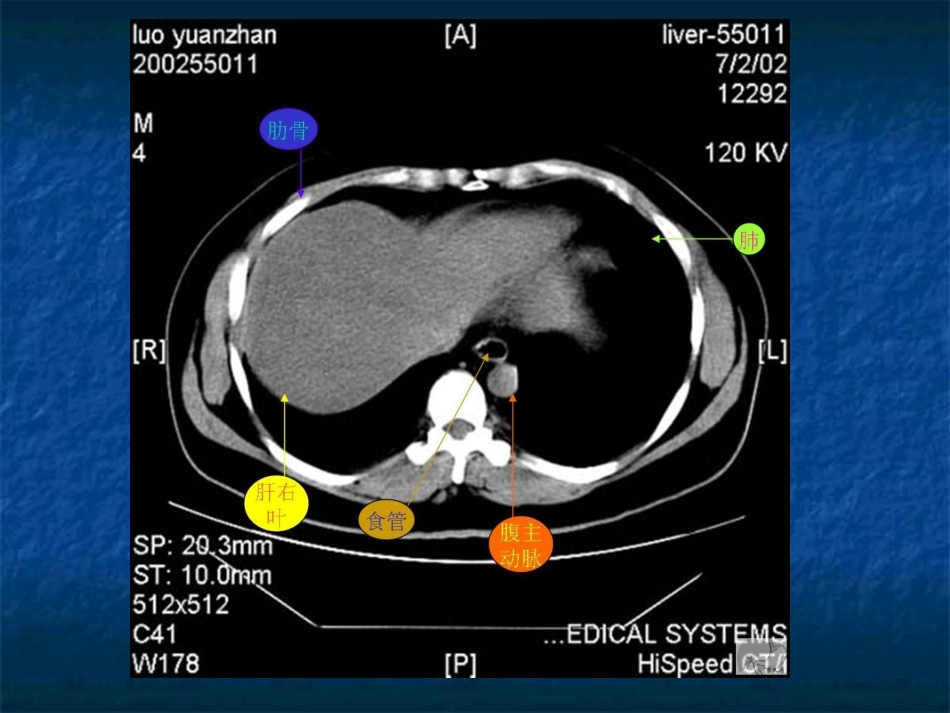

腹部腹部CTCT读片入门读片入门上上

腹部CT读片入门上